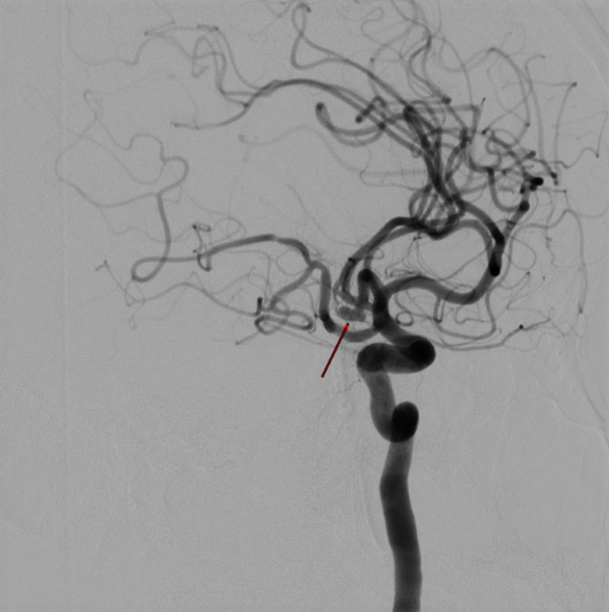

当天下午,董白晶就为叶女士进行了介入治疗,将导管从大腿根部的血管内伸进去,到达脑动脉瘤腔后进行填充:“动脉瘤就像血管长出的一个口袋,介入治疗就是要把这个口袋填满,让血流能按照正常的流向流动,不再流入口袋。”

术前血管造影